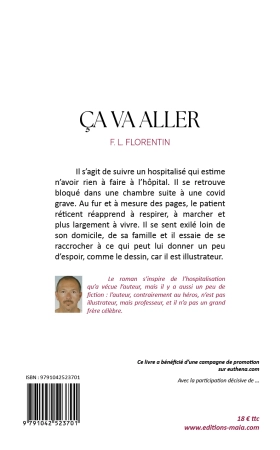

Ça va aller est un titre ironique car le livre débute quand rien ne va plus dans la vie de cet illustrateur connu sous le pseudonyme de Crayon. Lui, qui reste toute sa journée assis devant sa planche à dessiner, ne comprend pas pourquoi, à cause de ce stupide virus, il ne peut plus ni marcher ni respirer tout seul. Cette chronique suit donc les (més)aventures du héros lors de son hospitalisation et les répercussions de cette dernière sur sa femme et ses deux enfants.

F.L Florentin n’est pas un illustrateur, il n’a pas de grand frère célèbre, il est juste professeur d’histoire-géographie dans un collège. Mais l’histoire qu’il raconte a des relents autobiographiques : il a effectivement été hospitalisé à cause d’une COVID grave et il s’est senti obligé de témoigner de ce qu’il avait traversé durant cette épreuve. C’est durant son hospitalisarion qu’il a commencé à écrire le brouillon de Ça va aller.

Un père de famille est hospitalisé à cause d’une COVID grave. Il ne comprend pas ce qu’il fait là : il a tout le temps porté un masque dès qu’il sortait, il s’est fait vacciner régulièrement … et pourtant il est là, à ne plus pouvoir ni respirer, ni marcher, dans le service réanimation de l’hôpital, cloîtré dans son lit. Seul la plupart du temps et immobilisé, il tente de survivre en dessinant - le héros est illustrateur - et en racontant ce qu’il vit. Le roman suit sa lente réadaptation au monde autour et son indispensable rééducation : le héros se retrouve à réapprendre à inspirer, expirer ou à poser un pied devant l’autre, gestes - réflexes qu’ils croyaient définitivement acquis. Nous suivons donc le chemin, parfois tortueux, pour essayer d’aller mieux.